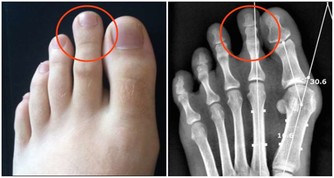

腳部出現青筋

腳面部位本來是平坦無皺紋的,如果表面出錢青筋凸起,說明腳部的血液循環開始出現受阻現象。雖然身體暫時感覺不到其他的不適癥狀,但是我們千萬不可以忽視這一癥狀。往往大病之前總是潛伏著一些小毛病。

腳部出現青筋,說明血液循環不暢通,但是前期人體並不會出現其他不適應的癥狀。沒有出現不適,不代表完全沒問題。血液循環不暢通,將會導致心臟部位無法及時接受身體回流的血液,繼而影響下一輪供血;還會導致腳部功能退化,出現足部組織壞死的現象。

所以,腳部出現青筋一定要引起註意,防患於未然總是疾病最好的對手。

靜脈曲張

靜脈曲張是指由於血液淤滯、靜脈管壁薄弱等因素,導致的靜脈迂曲、擴張。靜脈曲張的外在表現就是青筋暴起,並且長時間消退不了。靜脈曲張雖然聽起來可怕,但是人體並沒有其他不適,似乎不會影響正常生活,所以很多人並不重視。

其實這是非常錯誤的看法,靜脈曲張本身可能是其他病變的繼發表現,如靜脈閉塞。靜脈閉塞對身體的傷害可謂是致命性的,其對心臟的傷害可想而知